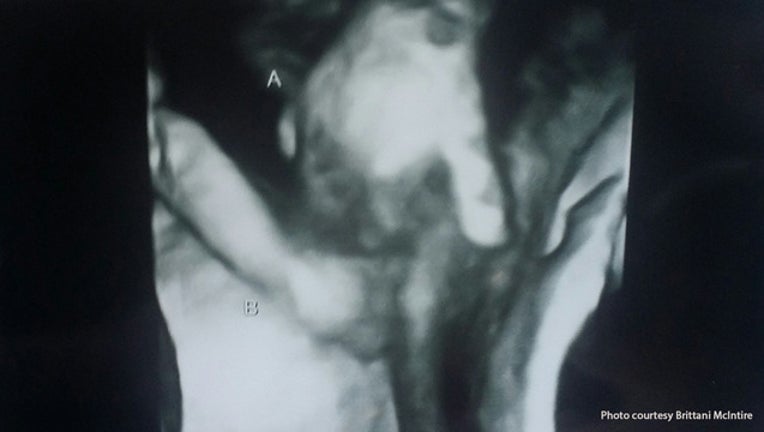

Touching sonogram image shows dying twin holding sister's hand

HUTCHINSON, KS -- A Kansas family has a touching moment during a very difficult time.  A sonogram this week shows a twin, who is not expected to survive, holding the hand of his sister in the womb.

Doctors say the boy has a hole in his heart and an abnormal brain.  The boy, named Mason, only weighs nine ounces while his sister, Madilyn, weighs more than two pounds.

"I know I'm holding him, I'm carrying him but I just want to be there for him. And knowing she's the only one who can actually be there and holding onto him through it, so it's comforting to know that if he does pass he won't be alone," Brittani McIntire says.